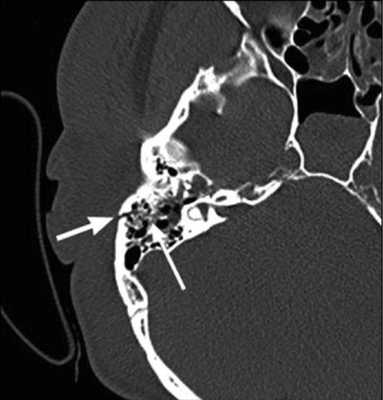

КТ височной кости при хондросаркоме

Височная кость является важной анатомической структурой - она участвует в формировании черепной коробки, здесь расположен слуховой аппарат, проходят крупные нервы и артерии. Обычные методы диагностики, такие как рентгенография или УЗИ, зачастую не позволяют диагностировать патологические изменения в этой области. КТ височных костей − более точное исследование, которое дает возможность выявлять заболевания на ранней стадии.

Во время КТ получают послойные снимки височной кости и окружающих тканей в трех плоскостях. Толщина среза составляет всего несколько миллиметров, что позволяет врачу-рентгенологу рассмотреть не только все анатомические образования, но и минимальные патологические изменения.

С помощью КТ височных костей можно выявить любые заболевания воспалительного, травматического, опухолевого характера. Метод применяется для диагностики следующих патологий:

На КТ-снимке виден перелом пирамиды височной кости (указан стрелками)